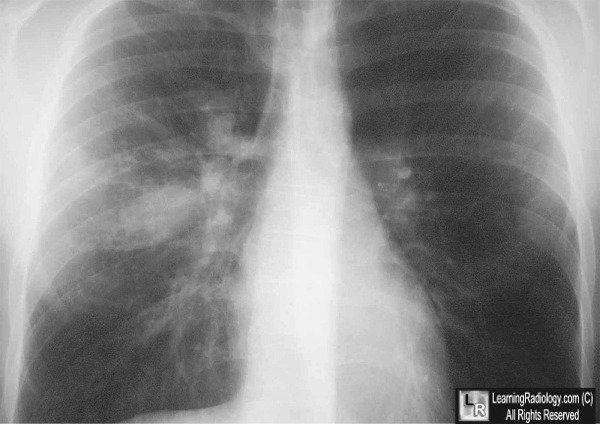

Chest Xray

X-Ray

If early, there may be no signs of infection on CXR

Classically, there is consolidation and mucoid impaction

Some notable signs include

Finger-in-glove opacities

"Toothpaste shadows"